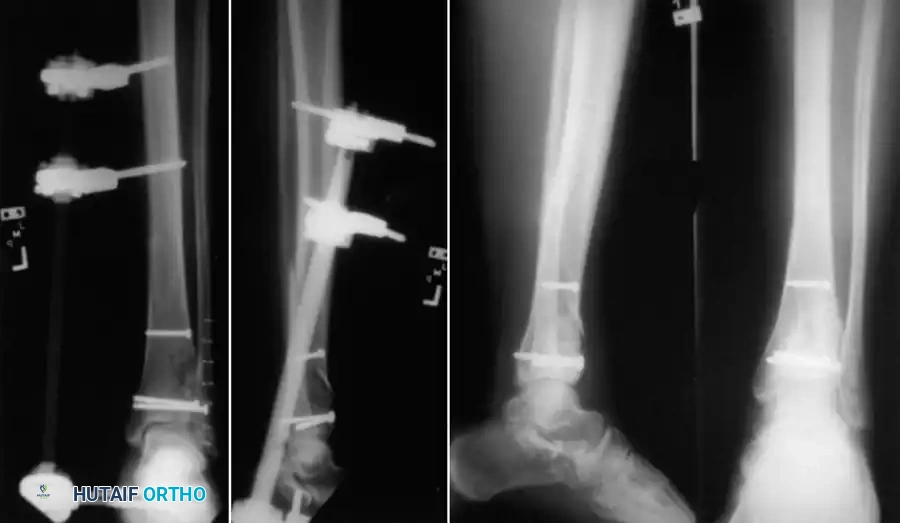

When an intramedullary nail, plate and screws, or external fixator is selected, the preoperative plan must rigorously account for the forces the fixation construct will sustain, the fatigue life of the implant, and the compliance of the patient. This biomechanical foresight dictates the postoperative rehabilitation program.

Küntscher originally described the fundamental biomechanical differences between pins, rods, and nails used for fracture fixation:

* Nails: Resist changes in alignment, translation, and rotation.